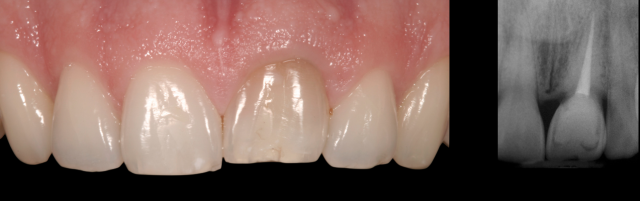

In contrast, the patient in Figure 2 is his mid-30s and also has tooth #9 ankylosed, but the gingival margin is level with the adjacent central incisor, leading us to conclude that it became an ankylosed tooth after growth was completed.